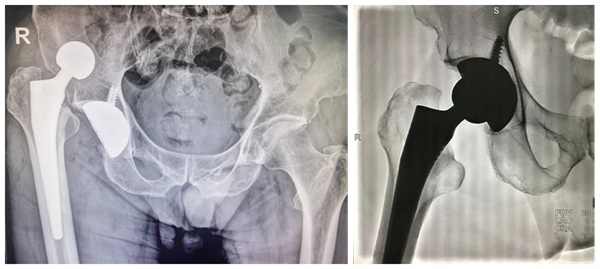

术前和术后X线片对比(左:髋关节脱位;右:成功复位)

外科病区赵波副教授通过详细查体及后续影像学发现,老邓系人工髋关节脱位,复位是唯一治疗手段。考虑老邓已年近七旬,合并2型糖尿病、骨质疏松症等,清醒状态下由于肌紧张直接复位难度较大,且复位时牵拉等操作会引发剧烈疼痛,患者难以耐受,如多次反复尝试复位不理想还存在意外骨折等风险。因此安排老邓办理住院,计划在麻醉状态下治疗。经外科病区张澍副教授、赵波副教授、主院区李浩鹏教授、王栋教授商讨后制定方案:全麻下优先尝试闭合复位,如失败则行切开复位,以确保万无一失。